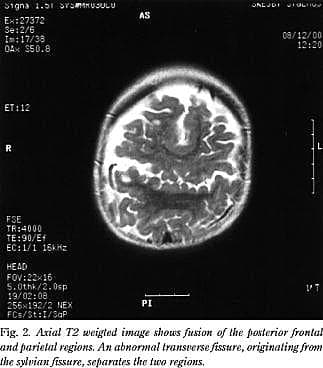

På grund af dysmorfologien og den forsinkede udvikling udførte man under anæstesi MR-scanning af cerebrum (Fig. 1 og Fig. 2 ). Scanningen afslørede et forstørret ventrikelsystem og septum pellucidum agenesia. Der fandtes mindre agenesi af begge temporalpoler. Corpus callosum var dysgenetisk med fraværende corpusdel. Der sås en sammenvoksning af den midterste del af de to storhjernehalvdele. Fissura sylvii fortsatte i en fissur frontoparietalt henover ventrikelsystemet og forbandt de to fissurer med hinanden. Der var ingen kortikale dysplasiforandringer eller heteropier. Der var normale myeliniseringsforhold og basalganglier. Billedet var foreneligt med middle interhemispheric fusion, også kaldet syntelencefali.

Synonymet middle interhemispheric fusion, skyldes den tilsyneladende sammenvoksning af den midterste del af hjernehalvdelene. Tilstanden betragtes som en mild form for holoprosencefali.